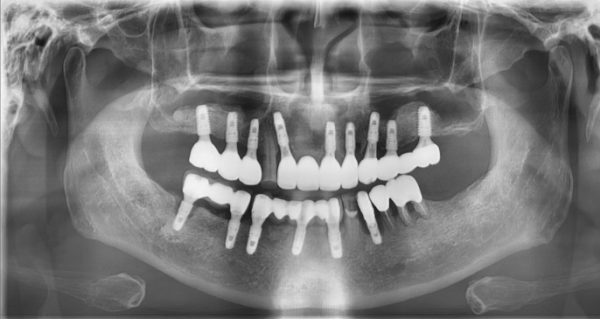

일반적으로 임플란트 주위에 세균 감염이 발생하여 치조골이 손상되면,

기존 임플란트를 제거한 후 상당한 기간을 기다려야 합니다.

제거 후 3~4개월 정도 기다린 뒤 재식립을 권유하기도 하는데,

본원에서는 내비게이션 기술을 이용하여 더 나은 치료 결과를 위해 노력하고 있습니다.